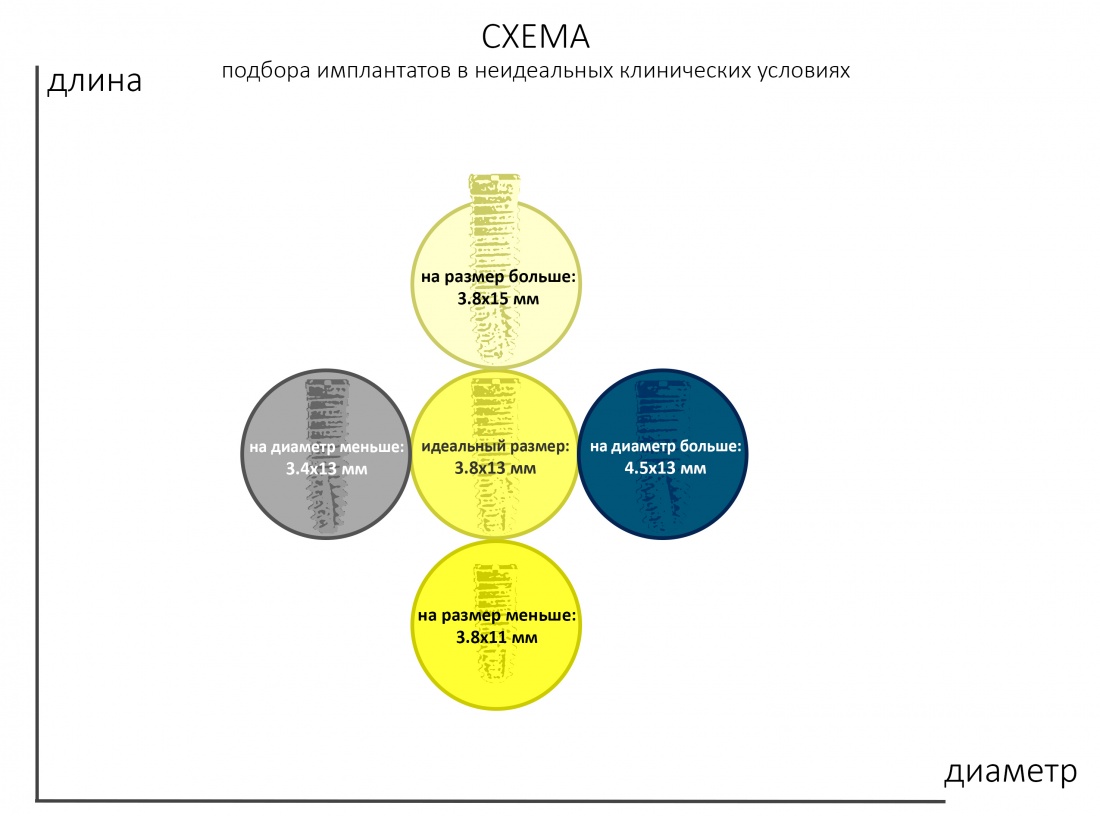

С неидеальными условиями всё несколько сложнее — та же немедленная имплантация несет в себе незначительную неопределенность, поскольку подбор имплантата (как и само решение о его установке) принимается только после удаления зуба. Это значит, что существуют варианты имплантатов

То есть, для «замены» одного зуба на имплантат, нам необходимы, как минимум, 5 имплантов, чтобы не испытывать проблем с подбором. Это, кстати, причина, по которой имеет смысл держать в клинике постоянно пополняемый склад имплантатов, а не заказывать их специально для каждой операции: